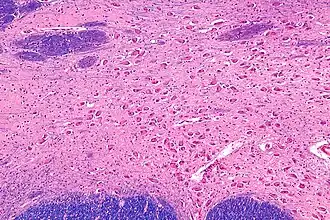

![]() Intermediate magnification micrograph of the nucleus basalis. LFB-HE stain. | |